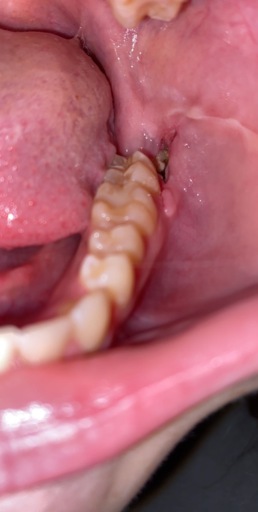

Do I need a biopsy? Is this a mucucele?

See pics please. This is soft to the touch. Been there a few years. I thought is was a blocked saliva duct but now it has the dark area beneath it which is new. Of note. About 6 years ago a general dentist said to keep an eye on it for any changes. He said it was most likely a mucocele (sp?) Again, it is soft to the touch.

See pics please. This is soft to the touch. Been there a few years. I thought is was a blocked saliva duct but now it has the dark area beneath it which is new. Of note. About 6 years ago a general dentist said to keep an eye on it for any...